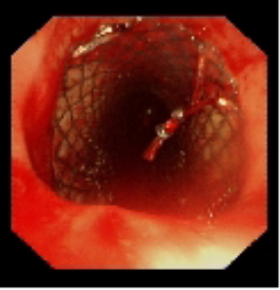

術前氣管重度狹窄

術中植入金屬覆膜支架

針對患者氣道狹窄危象,呼吸與危重癥醫學科聯合麻醉科、醫學影像科等多學科團隊制定個性化方案。術中采用全身麻醉聯合喉罩通氣,通過硬質支氣管鏡與軟鏡協同操作,在狹窄段實施腫瘤冷凍切除,隨后精準植入Y型金屬覆膜支架。手術全程動態監測生命體征,最終支架釋放位置理想,管腔擴張充分。術后復查顯示氣道通暢性恢復,患者血氧飽和度穩定在93%-97%。